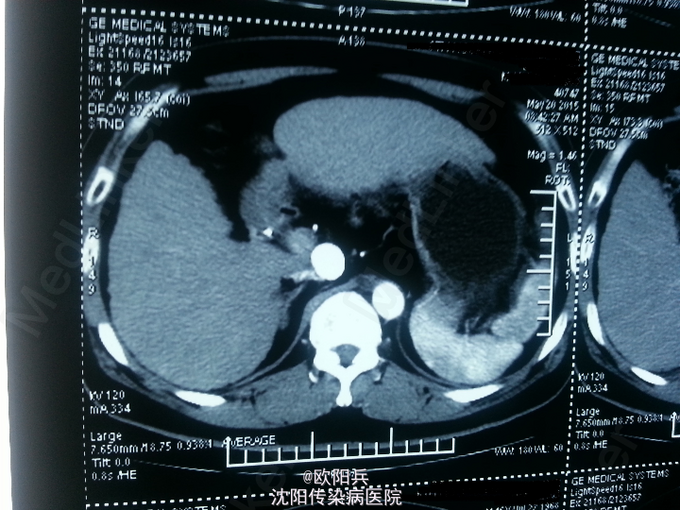

查体:神清语明,面色晦暗,巩膜无黄染,浅表淋巴结无肿大,心肺听诊无异常,腹软,无压痛,肝脾肋下未触及,移动性浊音阴性,肠鸣音正常,双下肢无水肿,扑翼样震颤阴性。 化验:血细胞分析(五分类):*白细胞计数 3.6 10^9/L、*血小板计数 113.0 10^9/L↓、*血红蛋白 166 g/L、中性粒细胞百分比 60.7 %,肝功酶谱:*丙氨酸氨基转移酶 92 U/L↑、*总蛋白 75.0 g/L、*白蛋白 47.0 g/L、*总胆红素 24.0 umol/L↑,糖化血红蛋白检测:糖化血红蛋白 13.50 %↑,*葡萄糖测定:*葡萄糖 15.66 mmol/L↑,血清离子测定:*钾 4.61 mmol/L,肾功能检测:*尿素 5.25 mmol/L、*肌酐 47.3 umol/L↓,血浆氨测定:血氨 29.00 ,凝血五项:凝血酶原时间 9.5 秒↓,乙肝六项:乙型肝炎病毒表面抗原 阳性(+) ↑、乙型肝炎病毒e抗体 阳性(+) ↑、乙型肝炎病毒核心抗体 阳性(+) ↑,丙型肝炎抗体测定(发光法):丙肝抗体 0.01 S/CO,甲胎蛋白测定:甲胎蛋白 7.29 ng/mL。 心电图:正常。 彩超(2015-5-17我院门诊):肝硬化、脾面积大,肝右叶高回声性质待定。 CT:1、肝尾叶占位介入术后改变;2、脾大,肝硬化,肝内多发RN可能性大。

根据患者病史、临床表现及目前辅助检查分析诊断:1、乙肝肝硬化 代偿期 活动性(C-P A级);2、原发性肝癌(肝尾叶)介入术后;3、2型糖尿病。主要诊断依据有: 1、患者乙肝肝硬化、肝癌介入病史明确,2型糖尿病史2年余。2、查体:面色晦暗,移动性浊音(-)。3、化验:患者肝功示转氨酶升高,无低白蛋白血症,C-P评分5分,支持乙肝肝硬化 代偿期 活动性(C-P A级)。糖化血红蛋白 13.50 %↑,葡萄糖 15.66 mmol/L↑,支持2型糖尿病。关于鉴别诊断,患者无酗酒史,不考虑酒精性肝病。其肝癌经DSA下肝动脉造影证实,无需鉴别。患者复查增强CT示肝尾页栓塞密实,边缘无强化,可暂无进一步处理,定期复查。本次住院行常规护肝抗肿瘤治疗。

患者半年前行介入治疗,效果如图,此类患者需密切观察肿瘤进展,目前暂无特殊处理。